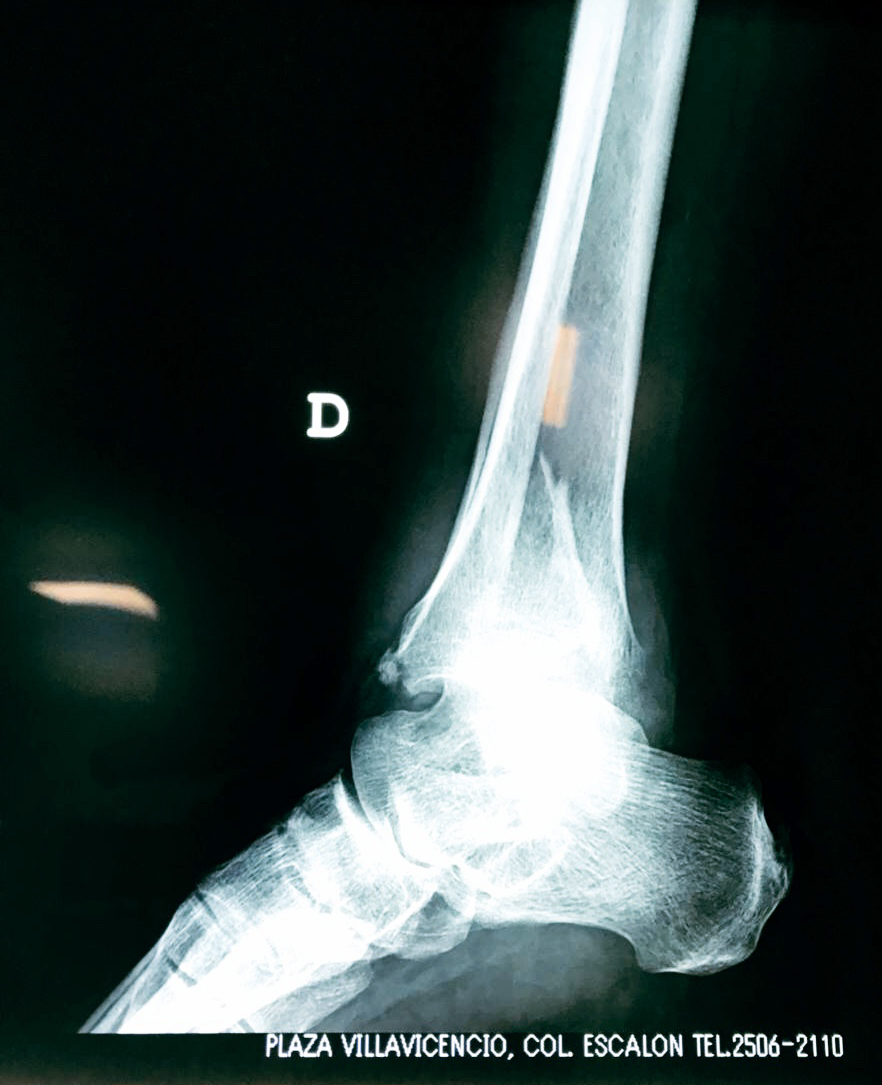

Una fractura de tobillo es la rotura de uno o más de los huesos del tobillo. Estas fracturas pueden ser:

- Parciales (el hueso está sólo parcialmente fisurado, no del todo).

- Completas (el hueso está perforado y está en 2 partes).

- Producirse en uno o ambos lados del tobillo.

Algunas fracturas de tobillo pueden requerir cirugía si:

- Los extremos de los huesos están desalineados entre sí (desplazados).

- La fractura se extiende hasta la articulación del tobillo (fractura intra-articular).

- Los tendones o ligamentos (tejidos que sujetan los músculos y los huesos entre sí) están rotos.

- El médico cree que sus huesos probablemente no sanen apropiadamente sin cirugía.

- El médico considera que la cirugía puede permitirle una recuperación más rápida y confiable.

- En los niños, la fractura involucra la parte del hueso del tobillo donde el hueso está creciendo.

Cuando se necesita cirugía, es probable que esta implique el uso de clavijas de metal, tornillos o placas para sostener los huesos en su lugar mientras la fractura se consolida. Los elementos de soporte pueden ser temporales o permanentes.